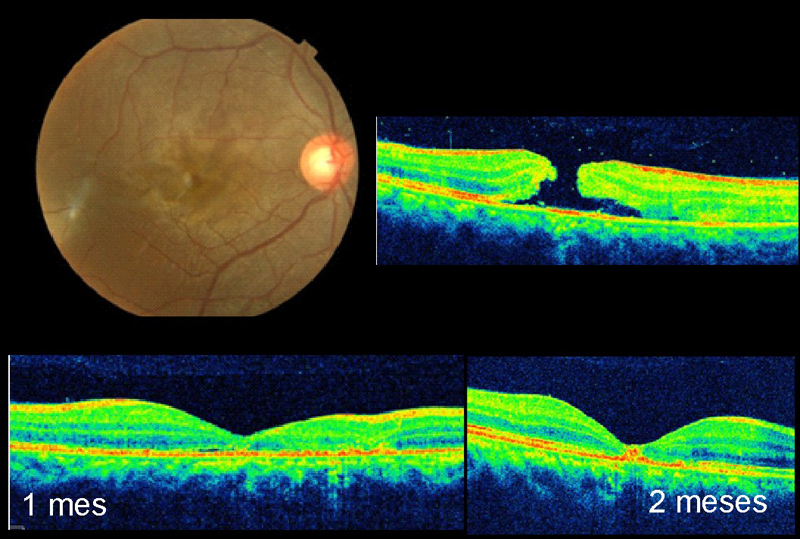

Cierre espontáneo

Es posible observar el cierre espontáneo en un 50% de las tracciones vitreomaculares con agujeros maculares incompletos (grado I en la antigua clasificación por OCT)

11 (

Figura 9), pero sólo se consigue la resolución espontánea en un 2% a un 4% de los agujeros de grosor completo (grados 2-4 de la antigua clasificación)

11,12.

Figura 9. Cierre espontáneo de agujero macular de grosor incompleto y tracción vitreomacular. Se objetiva un agujero que implica las capas externas de la retina, aunque no llega a ser completo en las capas más internas. Se produce un cierre espontáneo a lo largo de 3 meses de seguimiento. El paciente conservaba agudeza visual, pero refería metamorfopsias y leve escotoma central que se desaparecieron tras la resolución del cuadro.